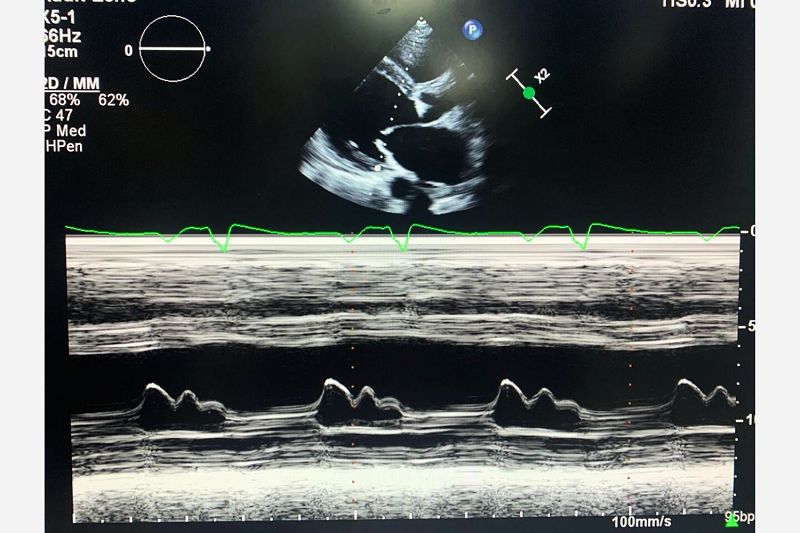

Image of the Week - 21 February 2024

Doctor Raid Faraj

Doctor Nouhaila Lahmouch

Doctor Jamila Zarzur